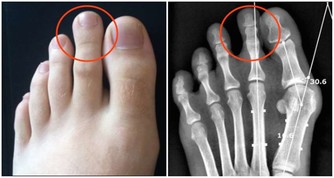

十三、身上的包塊,不痛的比痛的更危險

當發覺身上有了不明原因的腫塊,比如在乳房等位置,有紅腫熱痛的症狀往往只是單純的炎症,但是如果這個包塊不痛,而且活動性不好,也就是很固定,難以推離原有的位置,那麼惡性的可能性會暴漲。所以,身上發現不明原因的不痛腫塊,一定馬上去醫院